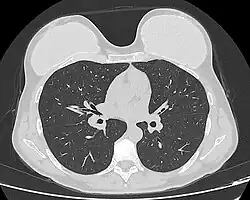

Computed tomography of a woman with breast implants

The study Safety and Effectiveness of Mentor's MemoryGel Implants at 6 Years (2009), which was a branch study of the U.S. FDA's core clinical trials for primary breast augmentation surgery patients, reported low device-rupture rates of 1.1 per cent at 6-years post-implantation.[57] The first series of MRI evaluations of the silicone breast implants with thick filler-gel reported a device-rupture rate of 1 percent, or less, at the median 6-year device-age.[58] Statistically, the manual examination (palpation) of the woman is inadequate for accurately evaluating if a breast implant has ruptured. The study, The Diagnosis of Silicone Breast implant Rupture: Clinical Findings Compared with Findings at Magnetic Resonance Imaging (2005), reported that, in asymptomatic patients, only 30 per cent of the ruptured breast implants are accurately palpated and detected by an experienced plastic surgeon, whereas MRI examinations accurately detected 86 per cent of breast implant ruptures.[59] Therefore, the U.S. FDA recommended scheduled MRI examinations, as silent-rupture screenings, beginning at the 3-year-mark post-implantation, and then every two years, thereafter.[25] Nonetheless, beyond the U.S., the medical establishments of other nations have not endorsed routine MRI screening, and, in its stead, proposed that such a radiologic examination be reserved for two purposes: (i) for the woman with a suspected breast implant rupture; and (ii) for the confirmation of mammographic and ultrasonic studies that indicate the presence of a ruptured breast implant.[60]

Furthermore, The Effect of Study design Biases on the Diagnostic Accuracy of Magnetic Resonance Imaging for Detecting Silicone Breast Implant Ruptures: a Meta-analysis (2011) reported that the breast-screening MRIs of asymptomatic women might overestimate the incidence of breast implant rupture.[61] In the event, the U.S. Food and Drug Administration emphasised that "breast implants are not lifetime devices. The longer a woman has silicone gel-filled breast implants, the more likely she is to experience complications."[62]